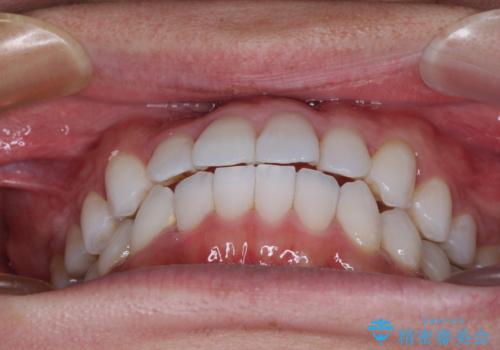

上顎側切歯(上の真ん中から2番目の歯)が舌側転位している場合、インビザラインでは仕上げきれない可能性があり、更には無理して動かそうとすると歯髄壊死を起こすリスクが高いと言われています。

安全に治療を行う対策として、インビザラインで歯列を移動する前に、上顎前歯をワイヤー矯正で整え、その後上下歯列をインビザラインにて矯正治療を行うプランを提案しています。

今回は、ワイヤー装置を併用することなく治療を行い、トラブルなく、満足のいく歯列に整えることができました。